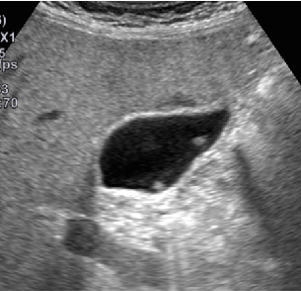

胃カメラであれば経過観察であっても、食道裂孔ヘルニアやバレット食道、胃ポリープと記載されていたり、腹部エコー検査であれば、肝血管腫やら胆嚢ポリープなどなど。

当クリニックのホームページでは、「消化器内科」や「当クリニックで行う検査」などの中に、健診でよく見かける病気について副院長が画像とともに分かりやすく説明をしています。